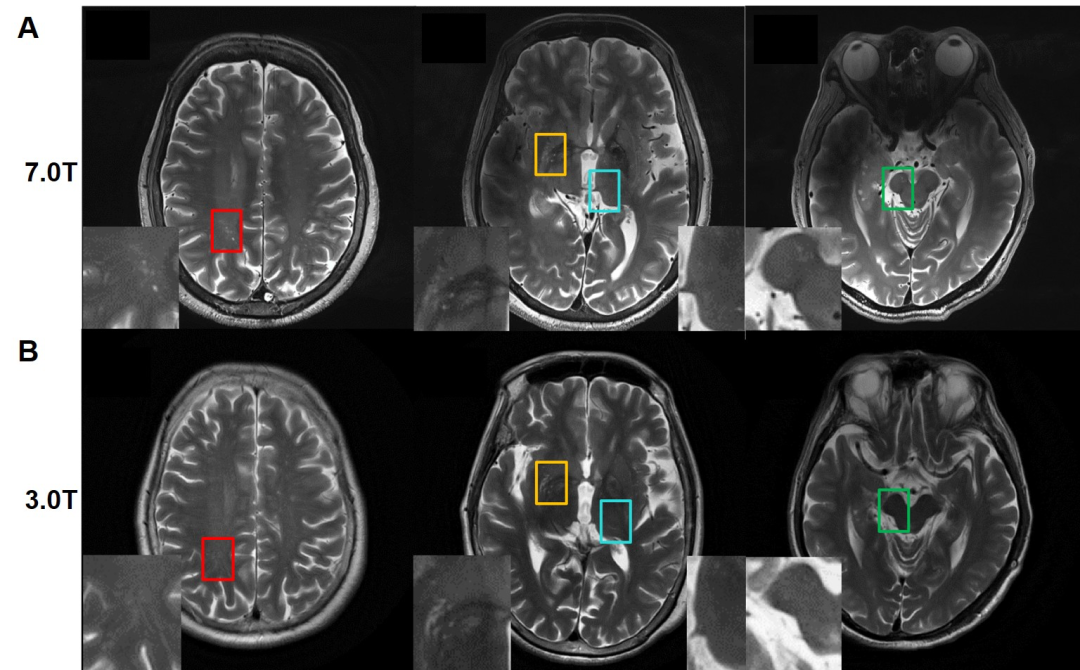

Comparison Of 3t And 7t Mri For The Visualization Of Globus Pallidus Sub Segments Scientific Reports